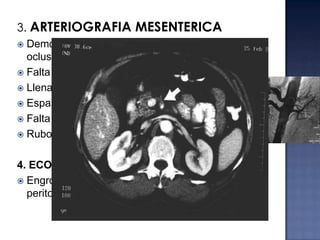

3. ARTERIOGRAFIA MESENTERICA

Demostración de un trombo en la VMS con

oclusión parcial o completa

 Falta de visualización de la VMS o vena porta

 Llenado lento o inexistente de las VM

 Espasmo arterial

 Falta de vaciamiento de los arcos arteriales

 Rubor

4. ECOGRAFIA

 Engrosamiento de pared abdominal y liquido

peritoneal libre = isquemia intestinal